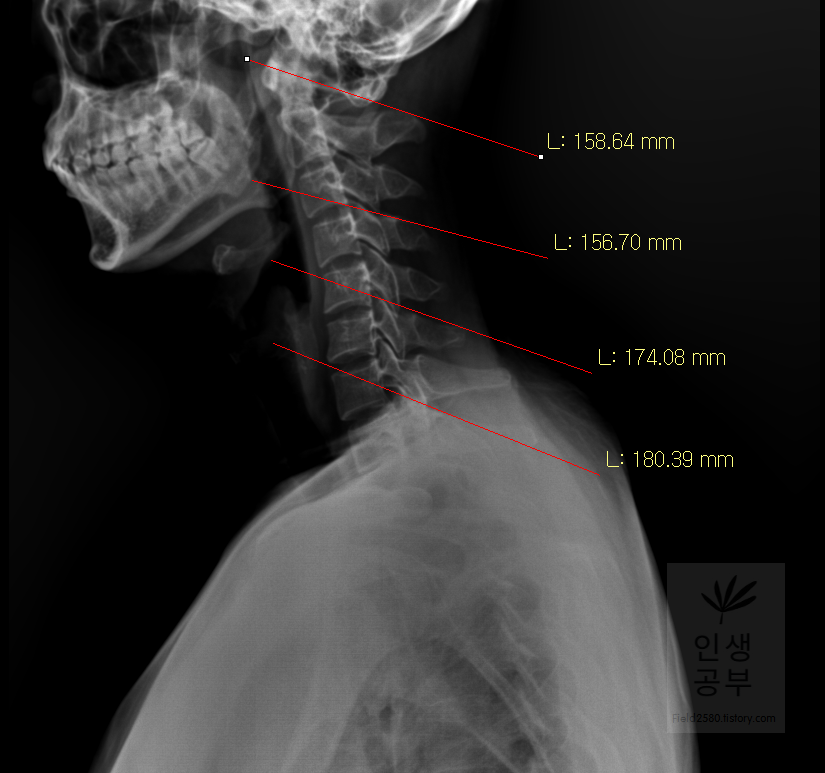

선 긋기를 이용해서 Cobb각을 그린다고 가정했을 때 측정하려고 하는 곳을 처음에 누르고 드래그로 쭉 끌어다주면 위와 같은 선이 생기고 선의 길이가 자동으로 측정됩니다. 첫 번째 목뼈(C1) 선을 그리기 위해 제일 튀어나온 앞쪽 부분 가운데 지점에(Center of Anterior arch) 점을 찍어줍니다. 후궁(Posterior arch) 제일 좁은 부위 가운데 지점에 점을 찍어줍니다. 두 점을 연결해주는 선을 그어줍니다. 이 선 이름을 고리 뼈 선(APL : Atlas Plane Line)이라고 합니다. 점은 조금 더 정확하기 위해서 하는 것이 찍어도 되고, 점을 찍지 않은 상태에서 선을 그으셔도 무방합니다.

일곱번째 목뼈 추체 밑면(Inferior endplate of C7)과 평행한 선을 그어줍니다.

위쪽에 있는 선은 첫 번째 목뼈(C1) 선을 그리기 위해 제일 튀어나온 앞쪽 부분 가운데 지점에(Center of Anterior arch)에서 시작해서 후궁(Posterior arch) 제일 좁은 부위 가운데를 지나는 선이 되도록 이동해줍니다. 선 이름을 고리 뼈 선(APL : Atlas Plane Line)이라고 합니다. 점은 조금 더 정확하기 위해서 하는 것이 찍어도 되고, 점을 찍지 않은 상태에서 선을 그으셔도 무방합니다. 아래쪽에 있는 선은 일곱번째 목뼈 추체 밑면(Inferior endplate of C7)과 평행하게 선을 맞춰줍니다. 노란색 글자와 숫자가 아래줄 맞춰 준 곳에 있는데 A는 Angle 각도이고 옆에 있는 숫자가 Cobb 각입니다.